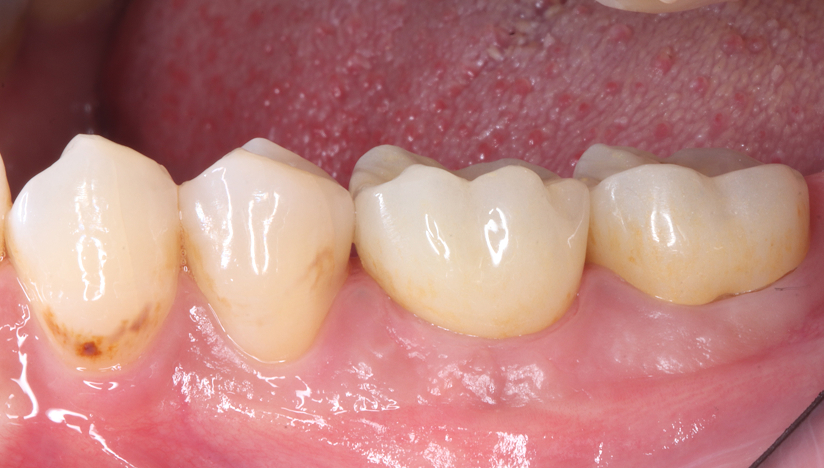

主訴

奥歯で噛めない、歯茎が腫れてきた

治療内容

抜歯即時インプラント埋入1本、待時インプラント埋入2本、リッジプリザベーション(顎堤温存術)、GBR

治療期間

6〜8ヶ月

治療費用

1,947,000

治療の

リスク

オッセオインテグレーションが得られなかった場合、撤去、再度埋入の可能性